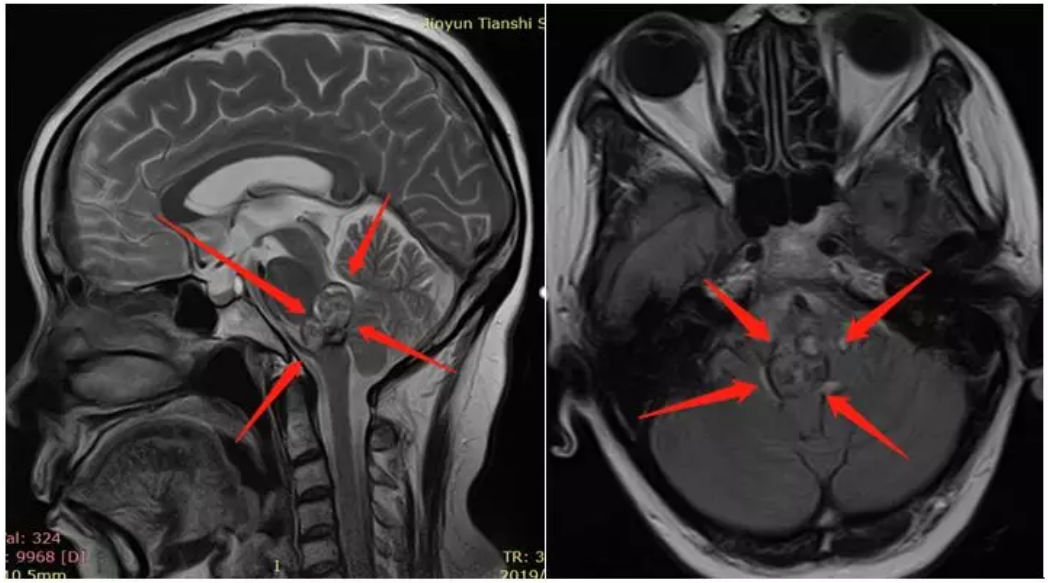

腦干海綿狀血管瘤出血案例術(shù)前診斷:腦干腦橋海綿狀血管瘤,出血活動期,壓迫四腦室

腦干海綿狀血管瘤出血術(shù)者:德國INI國際神經(jīng)學(xué)研究所Helmut Bertalanffy(巴特朗菲)教授

手術(shù)時間:2019年9月

手術(shù)地點:浙江大學(xué)醫(yī)學(xué)院附屬邵逸夫醫(yī)院

手術(shù)結(jié)果:顯微鏡下全切腫瘤,腫瘤切除歷時約1.5小時,手術(shù)順利。

ICU治療時間:1天,可完全自主呼吸,術(shù)后2天拔插管并轉(zhuǎn)出ICU病房。

術(shù)后48小時內(nèi)MR復(fù)查顯示腫瘤全切